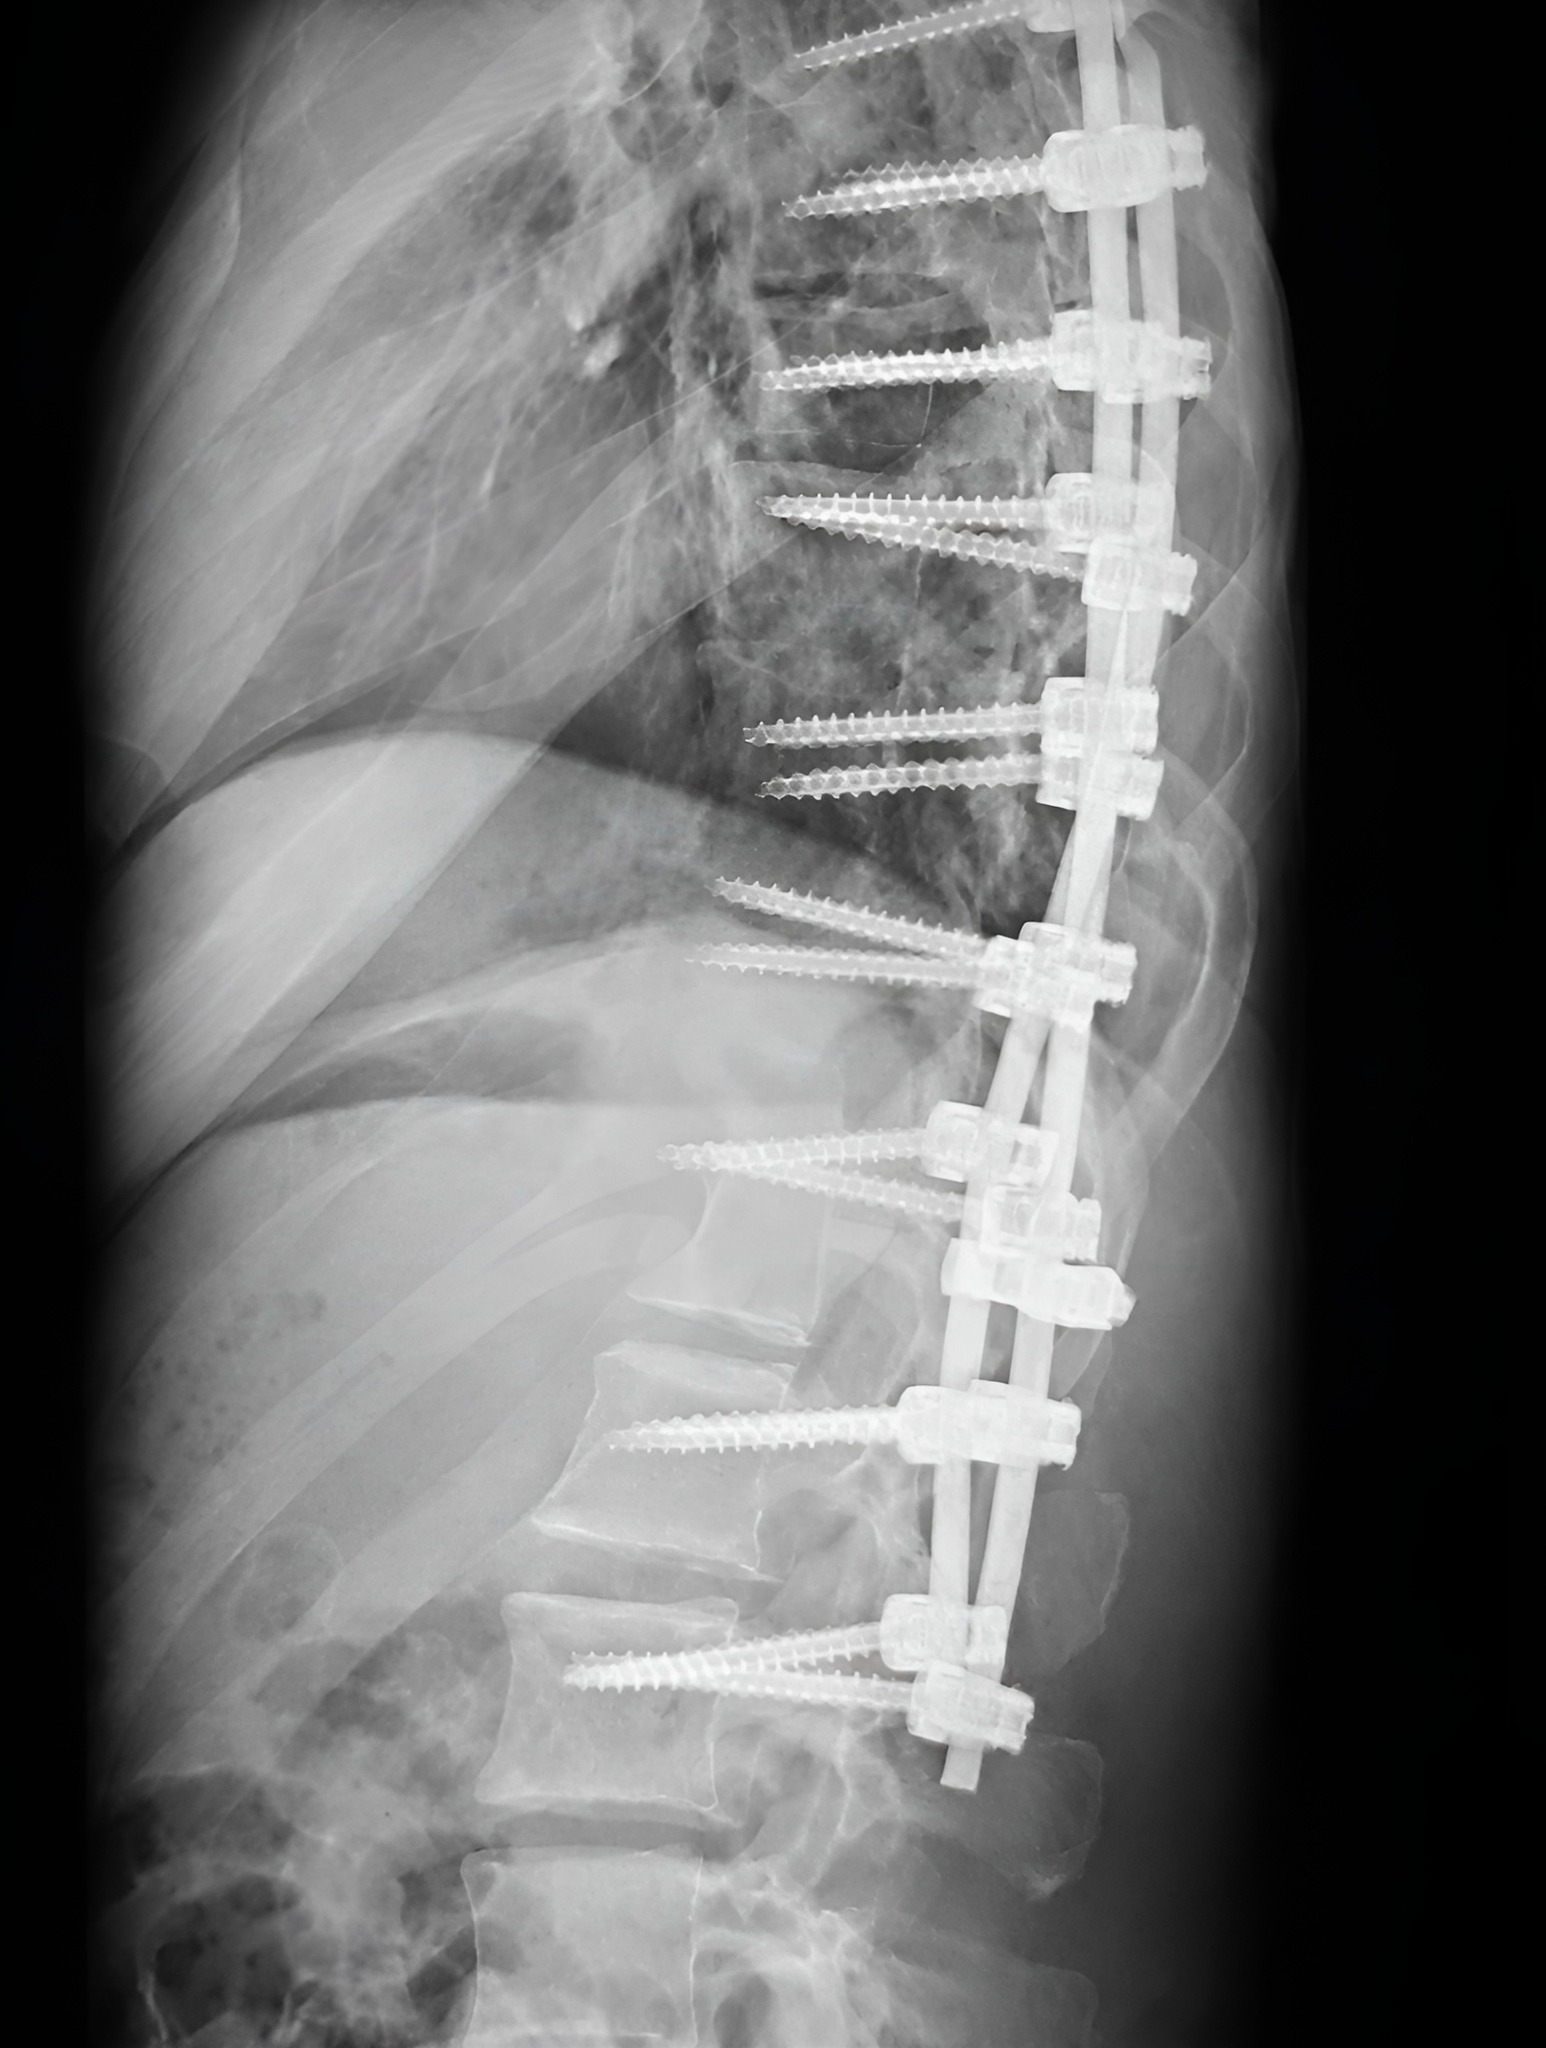

Помня този ден отпреди пет години. Или по-точно – не го помня. Не бях в съзнание. Затворих очи и следващият ми ясен спомен е събуждането в реанимация. Между тези два момента бяха изминали дванадесет часа под операционното осветление.

В следващите дни лежах сам в болничната стая, със силна болка и още по-силни въпроси. Размишлявах за бъдещето си. Лекари и специалисти от различни места даваха своите оценки. Много от тях си противоречаха. Най-тежки бяха онези прогнози, които говореха за трайни ограничения и невъзможност за пълноценен живот.

Бях парализиран от главата надолу, но усещах ясно парещите импулси на нервите си. Тялото ми беше неподвижно, а умът ми – активен. Питах се как ще изглежда животът ми след пет години. Дали ще се превърна в човека, който ми описваха – ограничен, физически слаб, зависим, принуден да се пази от всякаква активност до края на живота си – или ще избера да се хвана за думите на Бога и да им се доверя.